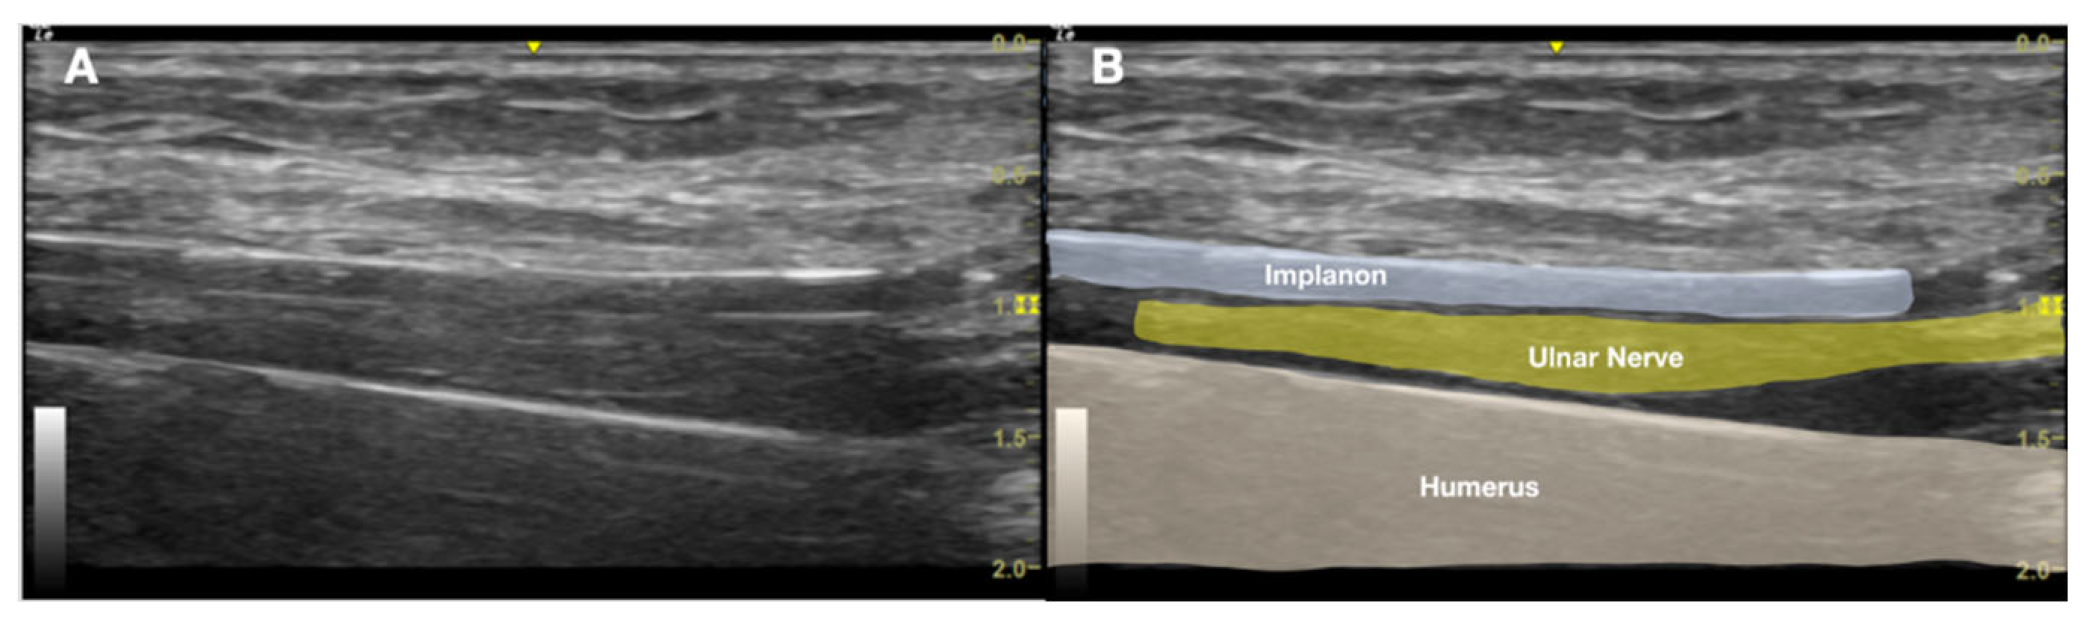

Figure 4. Long-axis ultrasound image of the medial arm demonstrating the Implanon® device positioned deep into the muscle layer adjacent to the ulnar nerve within the neurovascular bundle. A).Ultrasound image; B). Labeled explanation.

This radiographic confirmation prompted further evaluation with US imaging of the left medial arm due to clinical suspicion of implant-related nerve irritation. Using a high-frequency linear transducer (e.g. GE Linear L4-20t-RS General Electric, Boston, MA, USA), sonographic assessment revealed a linear echogenic structure with a reverberation artifact just above the medial humerus, approximately 5 cm proximal to the medial epicondyle.

The US findings localized the echogenic structure beneath the muscle layer, adjacent to the ulnar nerve, within the neurovascular bundle of the upper arm (Figure 4, Figure 5A). No neuroma or nerve enlargement was observed; however, dynamic US demonstrated apparent direct contact between the implant and the nerve sheath. The clinical impression was of a migrated, deeply seated, and unstable implant in close proximity to the ulnar nerve. Intermittent nerve irritation or impingement, likely exacerbated by daily movement and previous failed removal attempts, was considered the probable cause of her neuropathic pain. After obtaining informed consent, the decision was made to pursue minimally invasive, US-guided removal as an alternative to open surgical exploration.